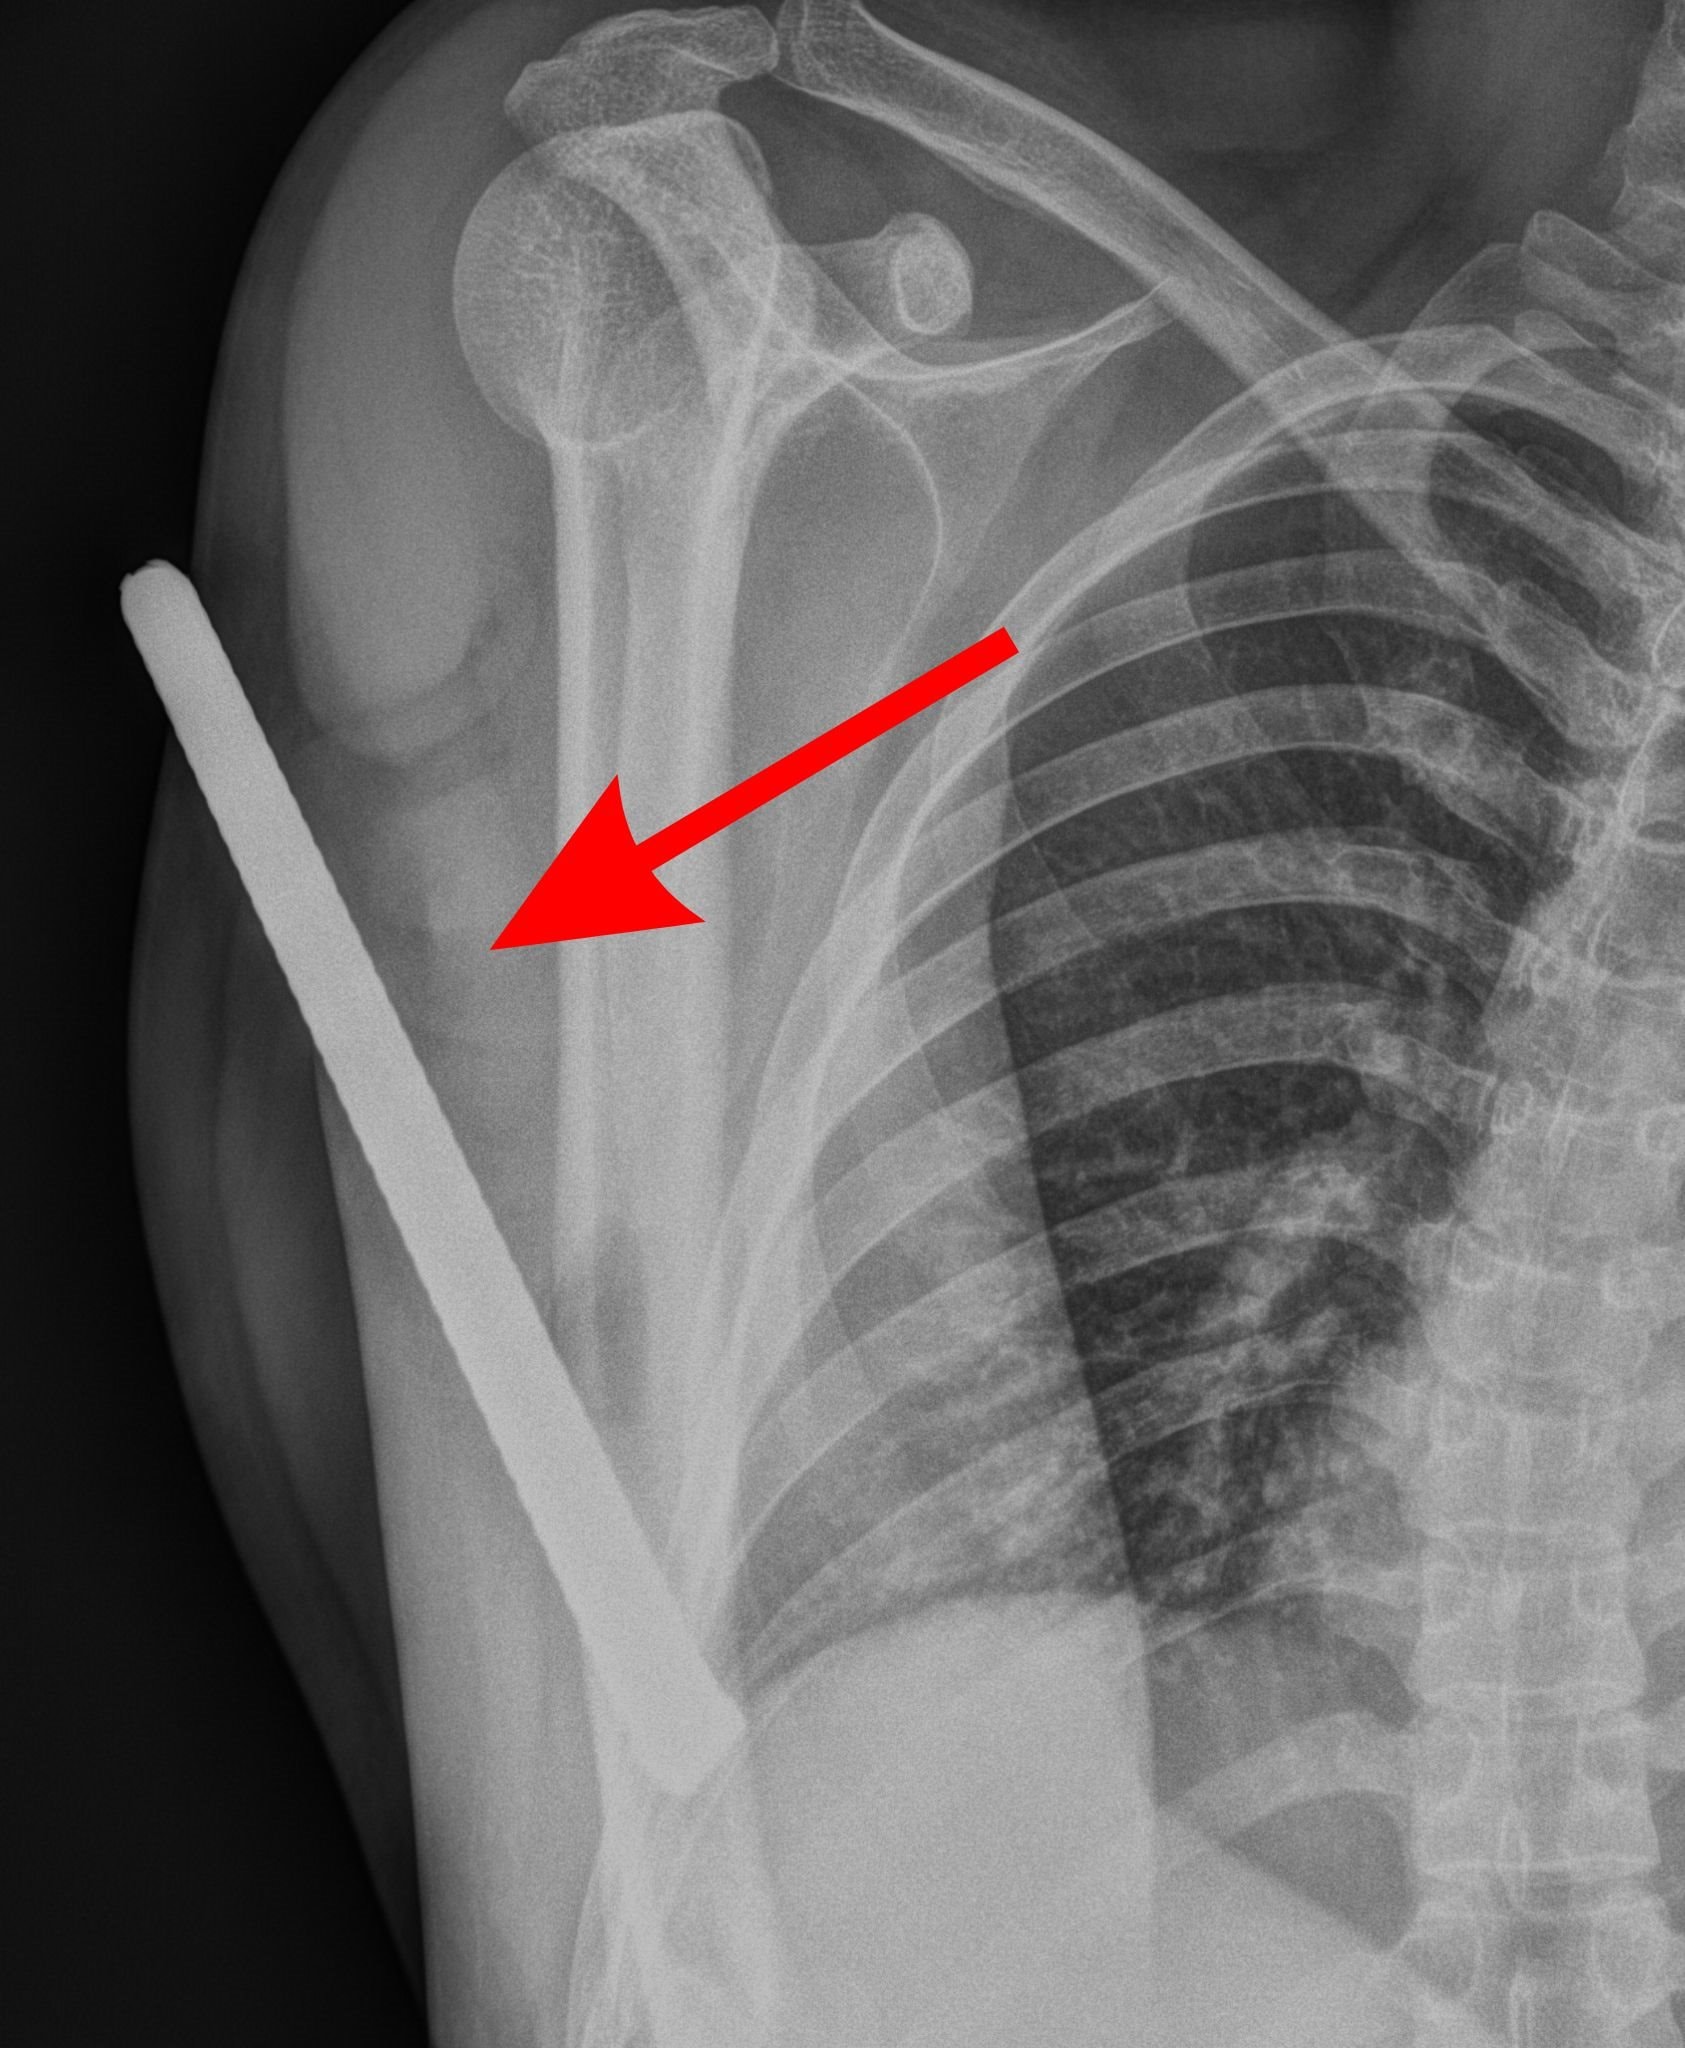

Tại đây, các bác sĩ ghi nhận dị vật xuyên từ mặt sau đầu trên cánh tay, chưa xác định được đầu còn lại.

Hình ảnh thanh sắt đâm xuyên cánh tay.

Kết quả kiểm tra cho thấy mạch máu chưa bị tổn thương nghiêm trọng, người bệnh vẫn cử động được cổ tay và các ngón tay, tuy nhiên vận động khuỷu tay bị hạn chế.